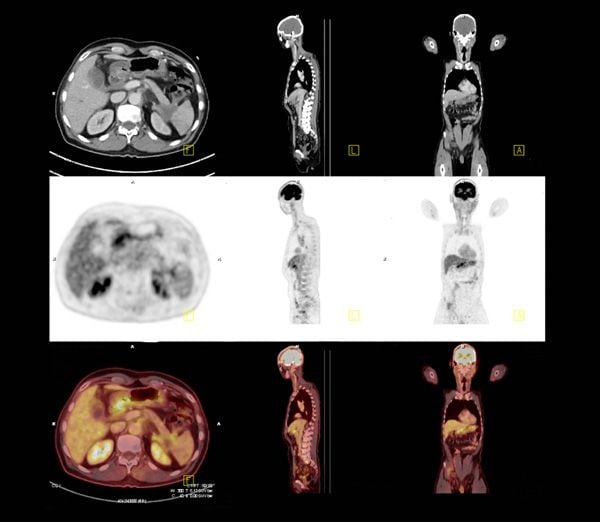

希林さんのように"がん"と付き合うコツ5